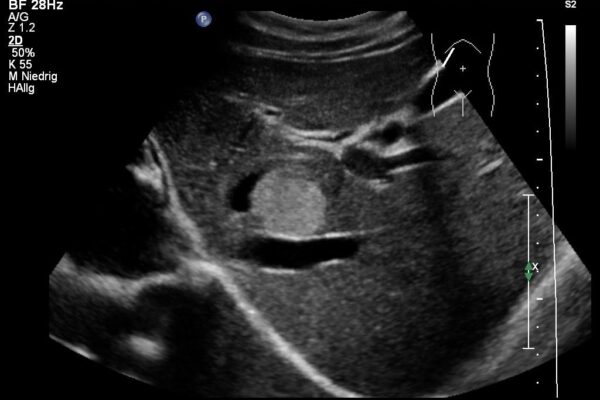

Die Bildgebung mittels Ultraschall (Sonographie) ist die am meisten genutzte, bildgebende Technik in der medizinischen Diagnostik. Dabei werden Schallwellen mit Frequenzen zwischen 1 und 40MHz benutzt. Die Ultraschallsonde (Schallkopf) sendet kurze Schallwellen aus, die im untersuchten Gewebe unterschiedlich stark reflektiert werden. Die reflektierten Schallsignale werden von der Ultraschallsonde wieder empfangen und vom Ultraschallgerät in Grauwerte auf dem Monitor dargestellt. So entsteht ein Ultraschallbild der inneren, von aussen nicht sichtbaren Organe und Strukturen. Dabei sind alle soliden oder blutreichen Organe (wie zB. Leber, Gallenblase, Nieren, Schilddrüse) und viele Gelenke (wie zB. Schulter, Knie, Hände und Füsse) gut untersuchbar.

Im Ultraschall der Bauchhöhle beurteilt der Arzt die Grösse, die Struktur und die Lage der Bauchorgane und Gefässe.

In den letzten Jahren wurde die Ultraschalluntersuchung bei Kindern das führende bildgebende Verfahren. Vom Säugling bis zum Jugendlichen können verschiedene Körperregionen schmerzlos und ohne schädliche Strahlung untersucht werden. Die häufigsten Ultraschalluntersuchungen bei Kindern und Jugendlichen betreffen den Bauchraum, hier wird nach zB. nach Ursachen für Bauchscherzen oder Harnwegsinfekten mit Fieber gesucht. Aber auch bei unklaren Schwellungen oder vergrösserten Lymphdrüsen bietet die Sonographie ein einfaches und schmerzloses Diagnosemittel. Zunehmend wird der Ultraschall auch in der Traumatologie (bei Unfällen) eingesetzt. So können Knochenbrüche mittels Sonographie diagnostiziert und der Einsatz von schädlicher Röntgenstrahlung minimiert werden.